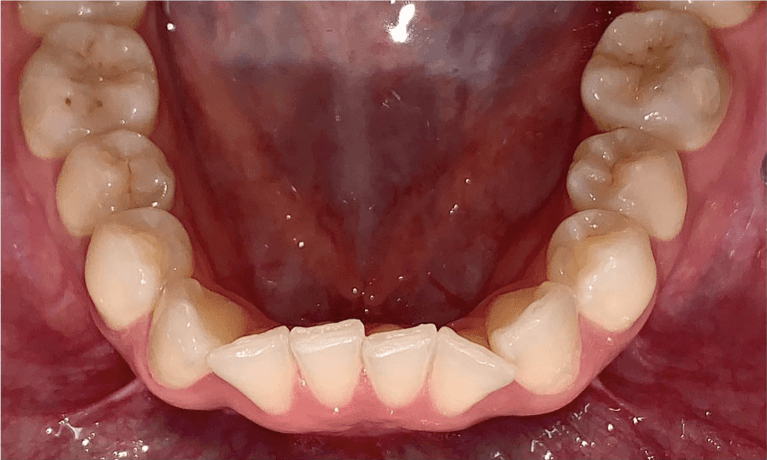

Before and after with Invisalign orthodontic treatment. Pictures taken with different phones at different setting. Used total of 27 aligners/trays. Treatment time 13.5 months